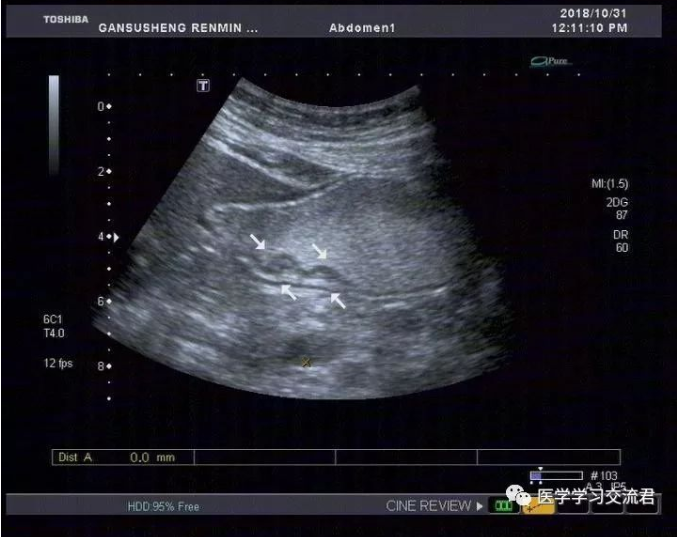

NO.3【胃肠超声造影】

嘱患者饮胃肠造影剂1000ml后扫查:胃贲门及幽门造影剂通过顺畅,胃窦后壁胃壁局限性不均匀增厚,累计长度约19.8mm,最厚处7.4mm,粘膜面连续性中断,可见6mm粘膜凹陷,其内见强回声斑附着,粘膜下层连续完整,局部胃蠕动僵硬,造影剂通过顺畅,余胃壁各层次清楚,粘膜光滑连续,蠕动良好,未见明显肿块及溃疡灶,十二指肠球部充盈好,内未见异常回声。

诊断:胃窦后壁胃壁局限性不均匀增厚并溃疡形成

(早期胃MT?或其他?)

根据2010年国际抗癌联盟/美国癌症联合委员会ICC/AJCC)TNM 分期标准并结合正常胃壁声像图表现得出超声下T分期标准:T1—病变局限于胃壁前三层(强—弱—强)回声线,未突破第三层强回声线;T2—病变侵及胃壁第四层弱回声线,但尚未突破该层结构;T3—病变侵及第五层强回声线但尚未中断;T4—病变突破第五层强回声线,甚至侵犯胃周组织。早期胃癌超声造影图像主要表现为:病变处胃壁局限性不均匀性增厚,回声减低,稍隆起于胃腔内或呈浅凹陷,局部胃壁黏膜层和黏膜肌层破坏、层次不清,与周围正常黏膜界限不清,黏膜表面不光滑或粗糙不平,有时可出现浅而大的黏膜凹陷,深可达黏膜下层,凹陷周缘胃壁水肿增厚,凹陷底部较宽而平,表面常附有不规则强回声斑,病变处胃壁蠕动减弱,局部有僵硬感。

该病例病灶浸润深度仅局限于胃壁的黏膜层或黏膜肌层,黏膜下层连续完整,与良性溃疡性病变在影像学诊断上有一定交叉重叠性,故需仔细甄别且须结合胃镜活检后的最终病理结果。